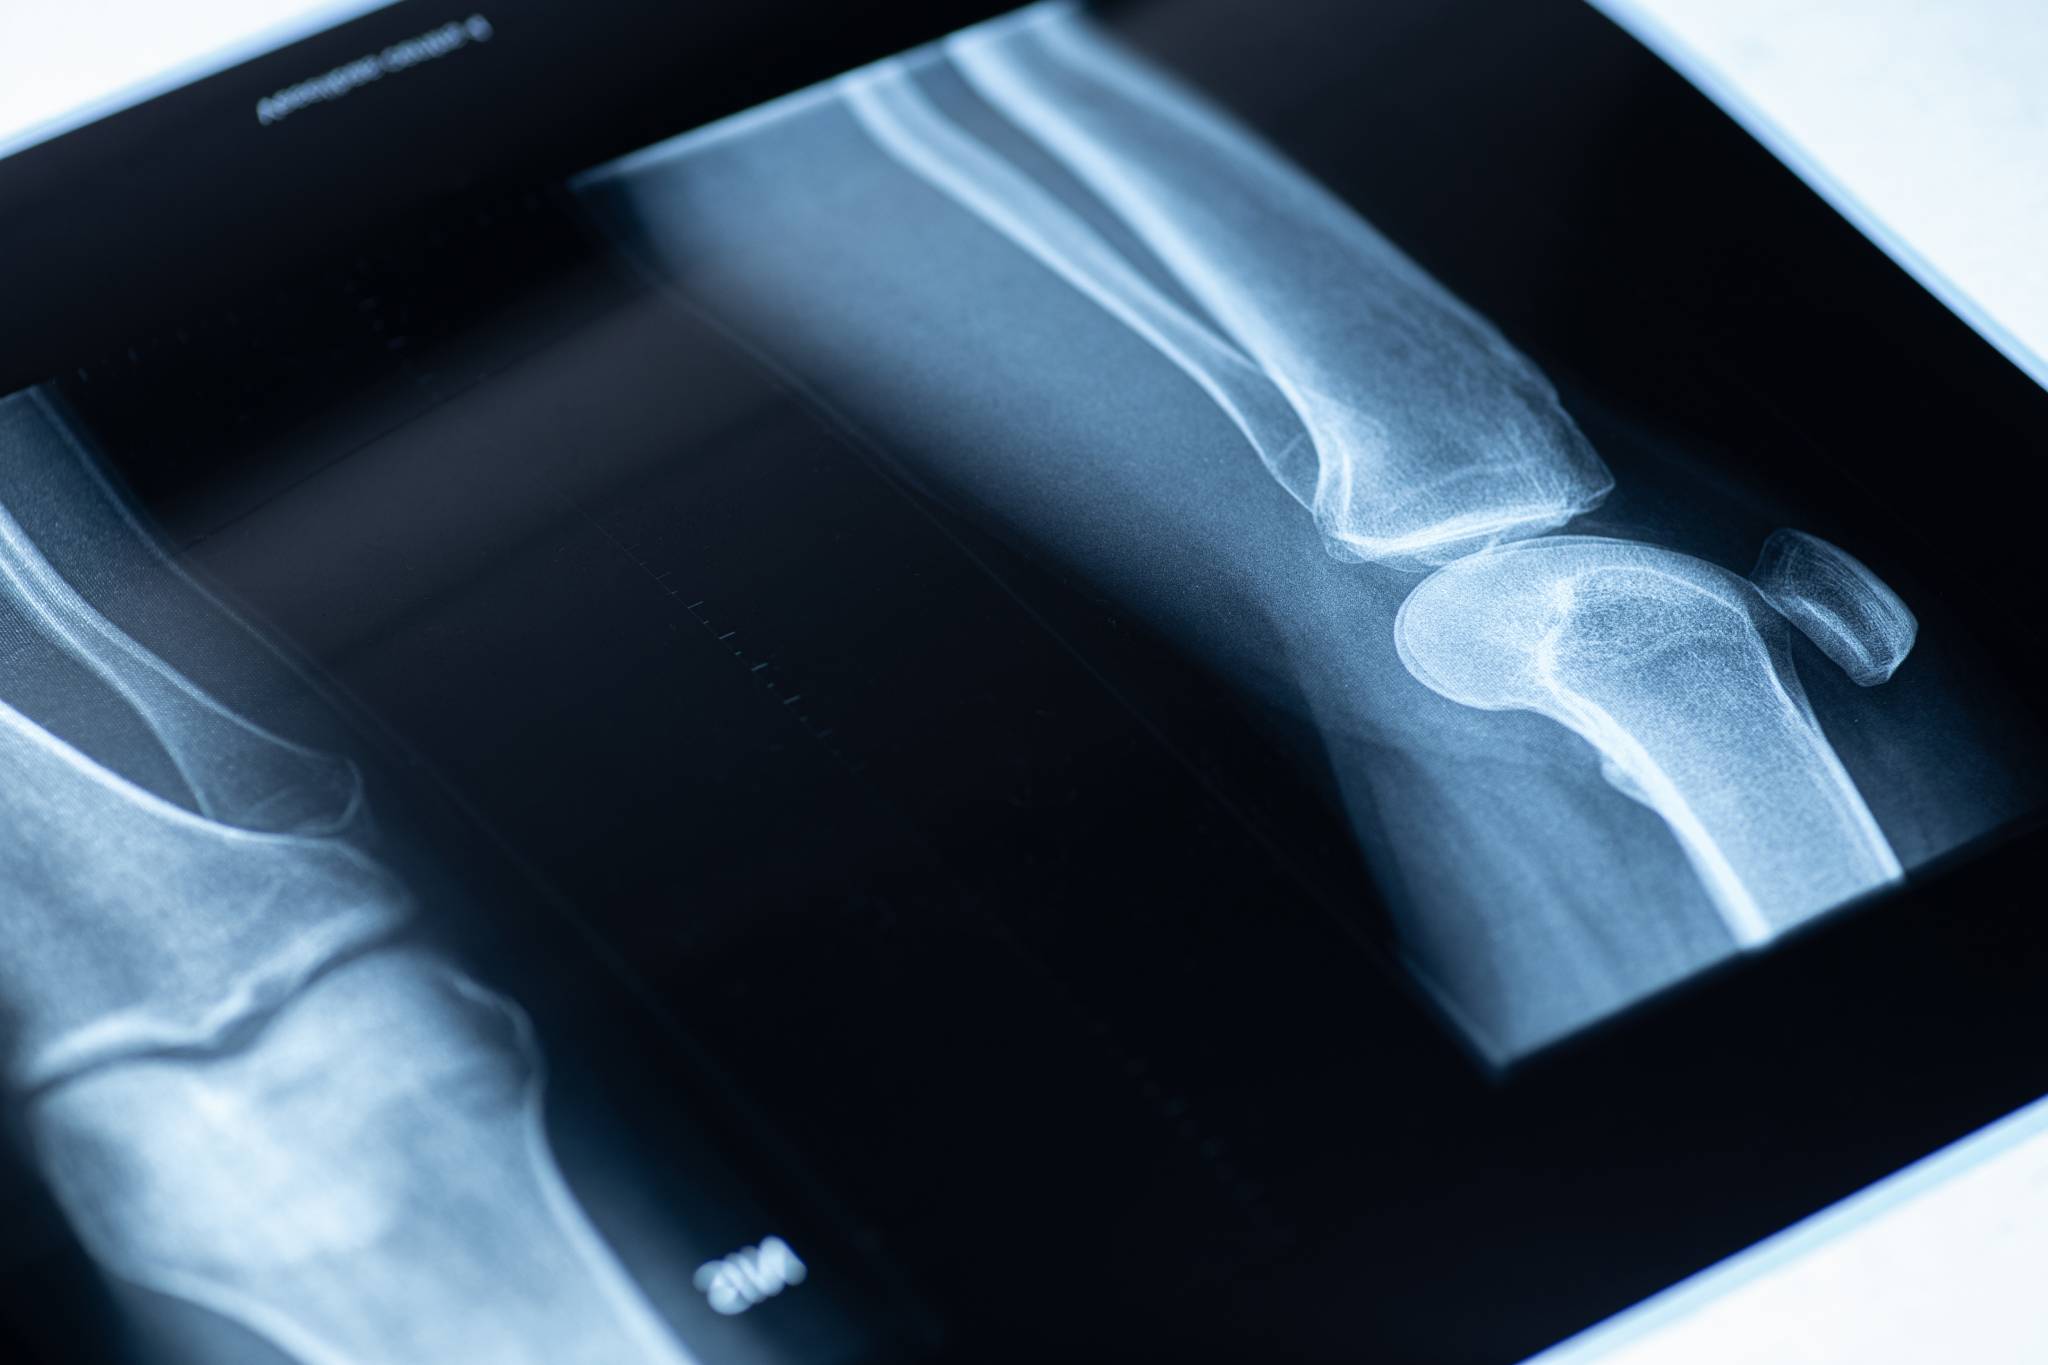

Tratamiento de fracturas

Osteosíntesis de fracturas recientes, no recientes, infectadas, o con consolidación viciosa.